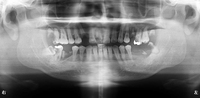

歯科治療の恐ろしさは、少しでも手を抜くと、積み重ねてきた治療効果が全て0=ゼロになってしまうことです。当院では一つ一つの治療過程にベストを尽くすべく、開業当初よりマイクロスコープ、セファロ分析や口腔内スキャンなど最新の機材を取り揃えて、幅広く、深い治療を追求してきました。

私はこれまでの歯科医師人生で、虫歯や歯周病、歯の根にある神経の処置である根管治療、入れ歯、インプラント、美容診療など、幅広く取り組んでまいりました。例えば虫歯治療では、痛みのある歯だけでなく、噛み合わせなどお口の中を総合的に考えたアドバイスや立案をし、歯を長持ちさせる処置を提供することを心がけています。